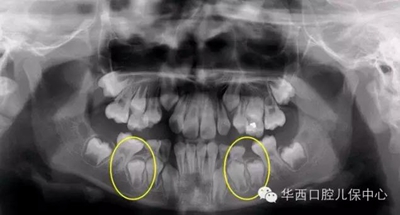

圖為下頜乳磨牙早失,未行間隙管理,繼承恒牙無法萌出(黃圈內(nèi))